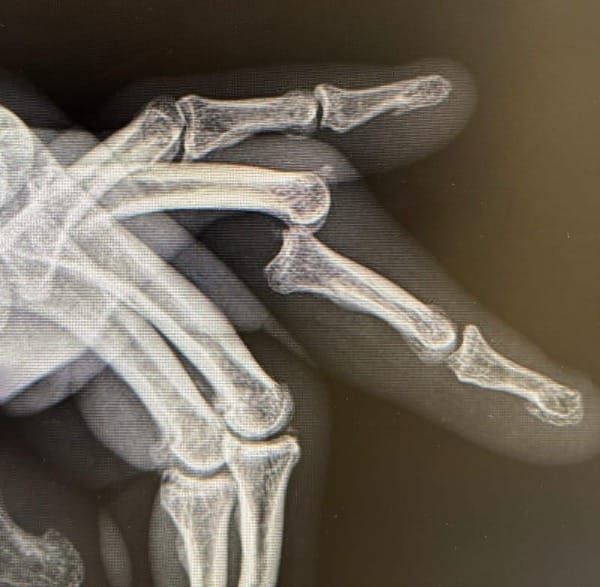

plastics@cases

Case of a 65 year old man with a recurrent volar PIPJ dislocation. Discussion of anatomical considerations and management.